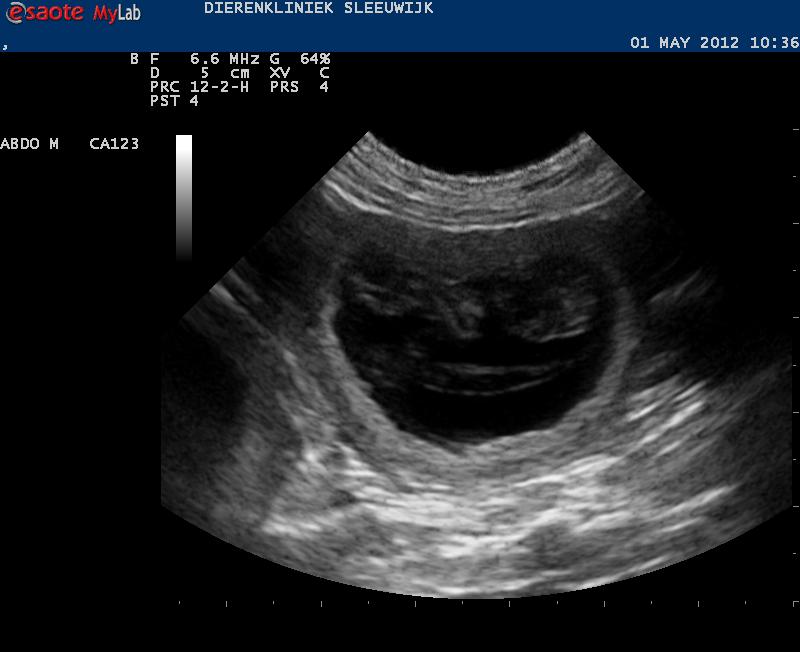

De afspraak voor de echo is gemaakt, ik hoop dat we begin volgende week het eerste bewijs van leven kunnen tonen.

In deze week veranderen de pupjes weer een heleboel: van ‘gekkootjes’ worden het steeds meer pupjes. De organen zijn bijna ‘af’. Zaken als tanden, snorharen, tenen en nagels worden duidelijker. De ogen krijgen oogleden. Het huidpigment wordt aangelegd: als we nu binnenin konden kijken zouden we kunnen zien hoeveel zwarte en hoeveel bruine pupjes Alba gaat krijgen, en of ze aftekeningen hebben.

Aan het eind van de week zijn ze 30 mm groot. De hoeveelheid vruchtwater neemt ook toe.